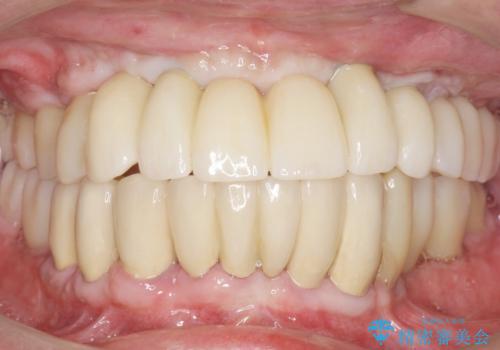

再生療法と骨外科処置により、歯周ポケットは全周2mm以下に改善されました。

保存が難しいと思われた歯を残すことができ、患者様にご満足頂けました。

補綴前に部分矯正を行うことで、歯の神経も保存することができました。

歯周病治療と連結補綴により歯の動揺がなくなり、「なんでも食べられます!」と喜んで下さいました。

生活歯(神経が生きている歯)のため形成量(歯を削合できる量)に限界がありましたが、熟練の技工士さんの素晴らしい技術により補綴を行うことができました。

クラウンの種類:メタルボンドクラウン エコノミー